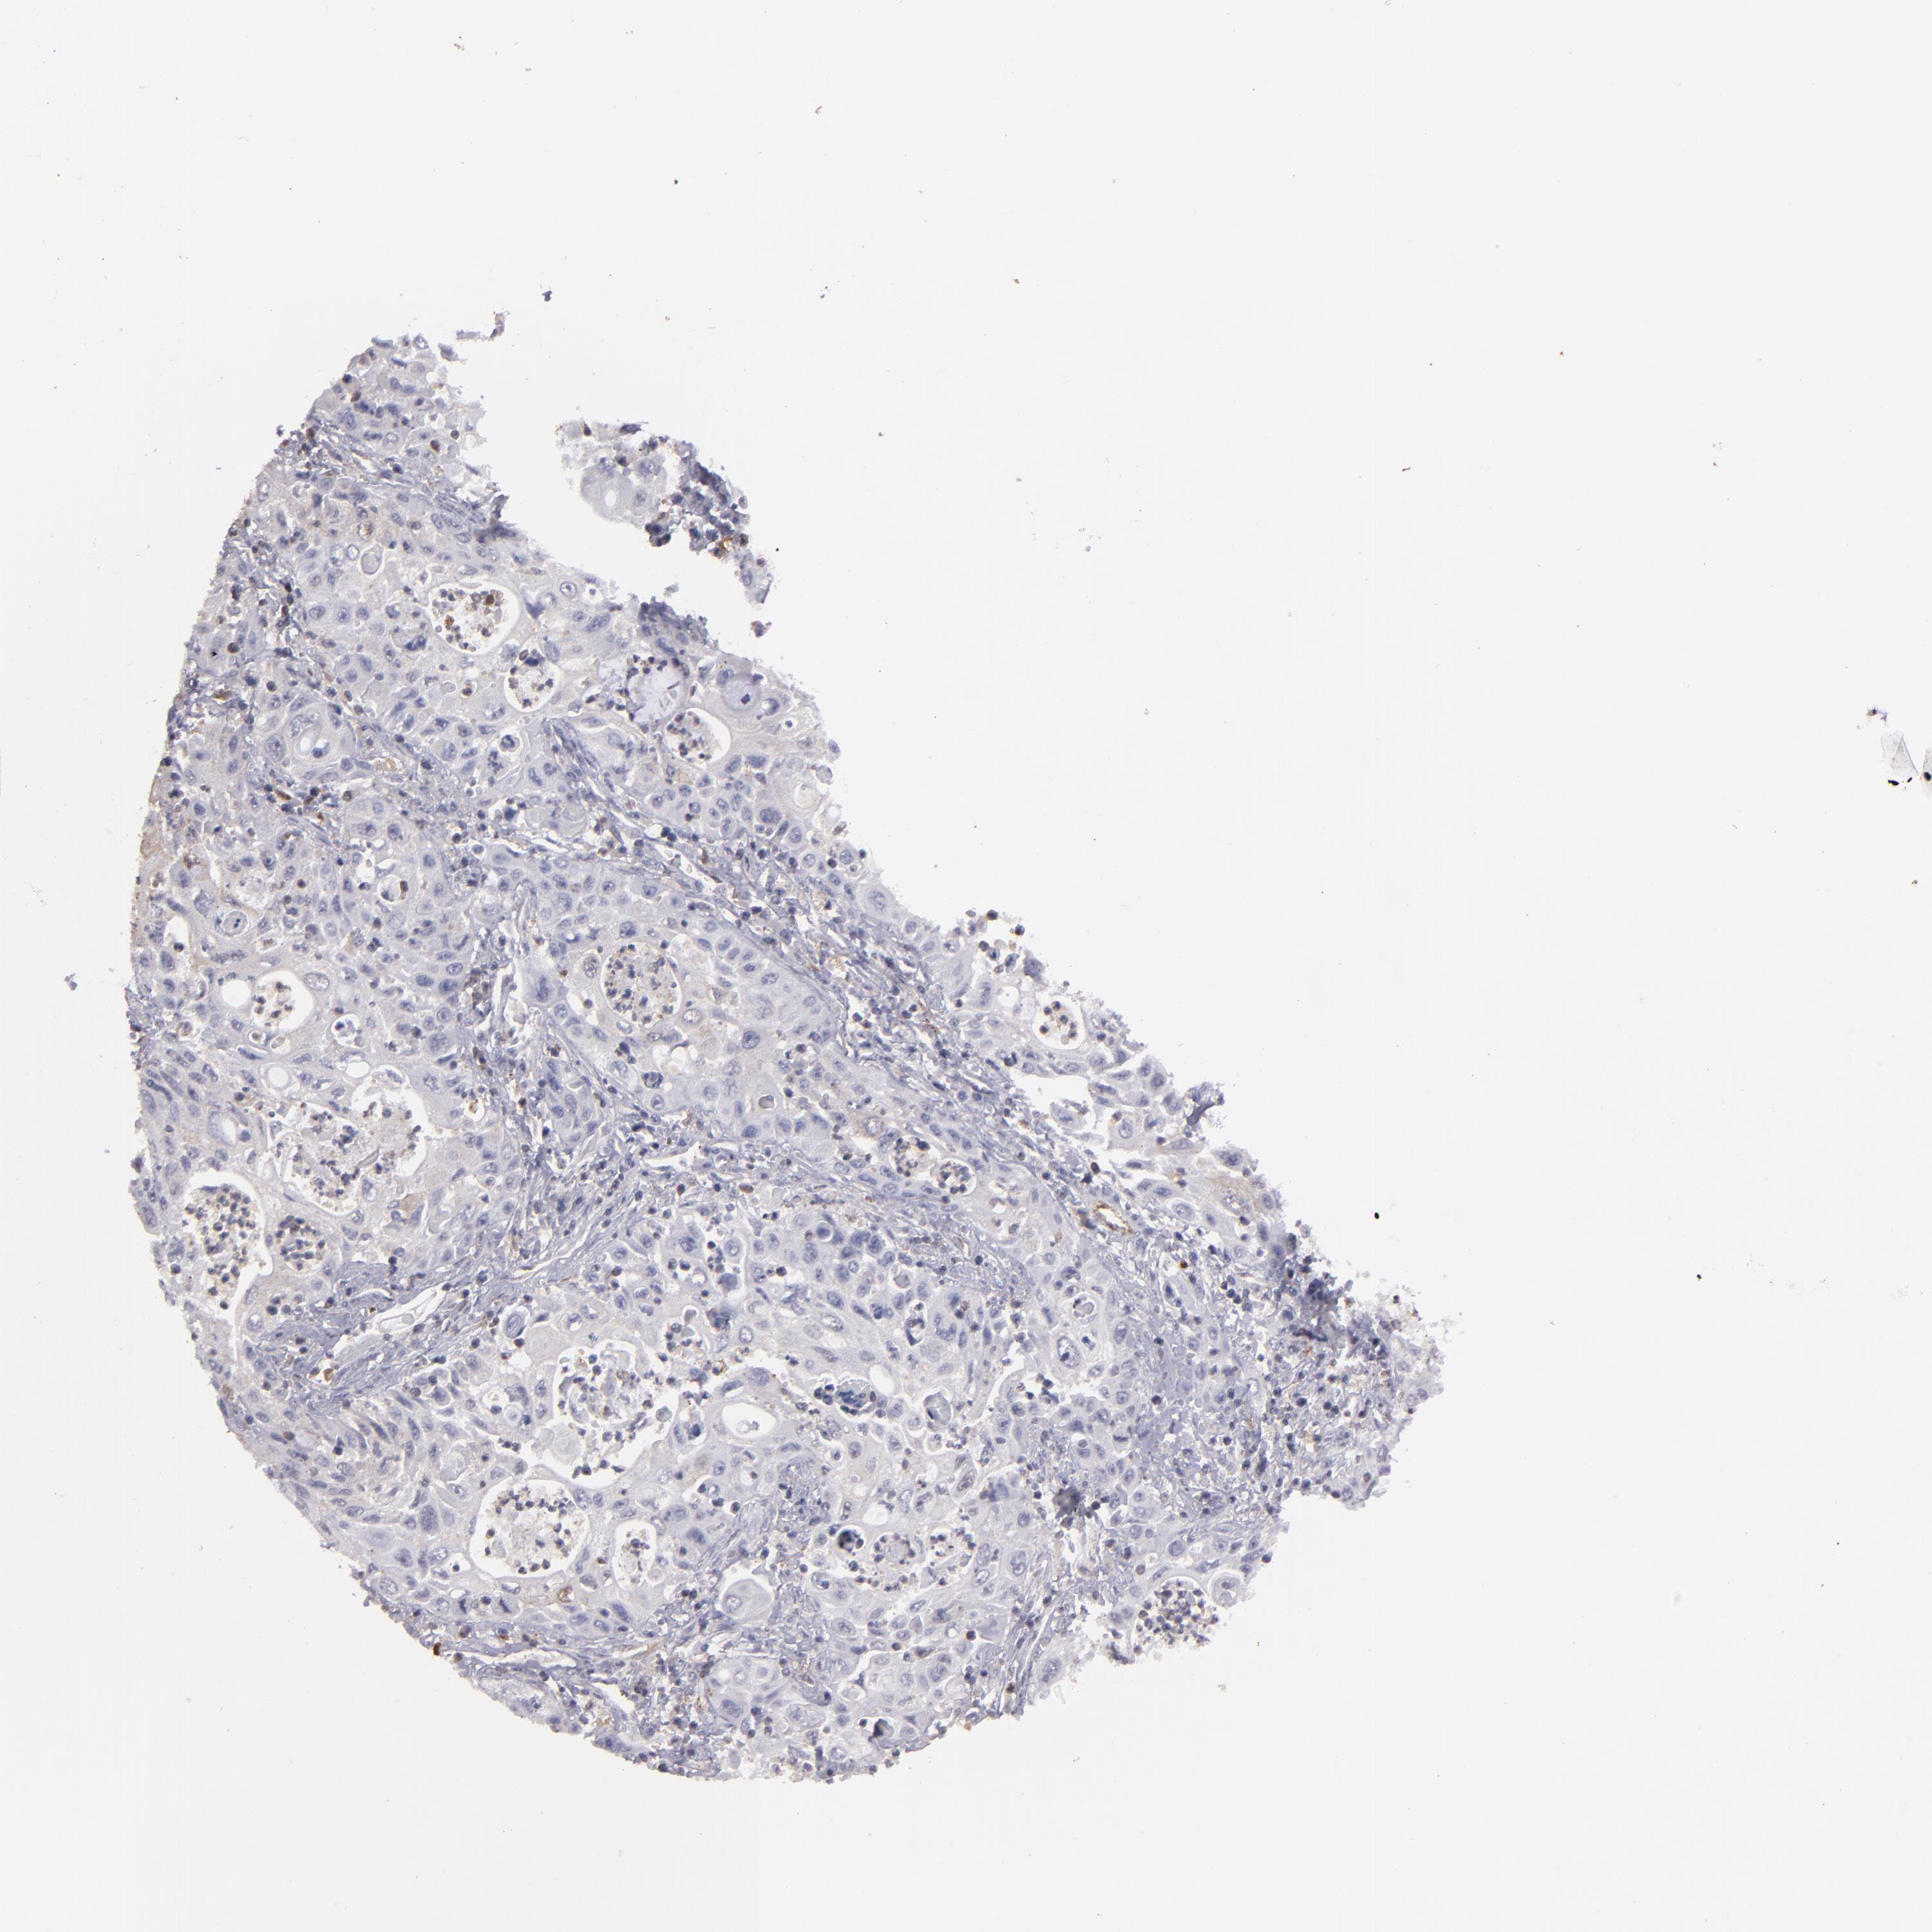

PANCREATIC CANCER - Protein expressioni

A mouse-over function shows sample information and annotation data. Click on an image to view it in a full screen mode. Samples can be filtered based on level of antibody staining by selecting one or several of the following categories: high, medium, low and not detected. The assay and annotation is described here.

Note that samples used for immunohistochemistry by the Human Protein Atlas do not correspond to samples in the TCGA dataset.

Antibody stainingi

Antibody staining in the annotated cell types in the current human tissue is reported as not detected, low, medium, or high, based on conventional immunohistochemistry profiling in selected tissues. This score is based on the combination of the staining intensity and fraction of stained cells.

Each image is clickable and will lead to virtual microscopy that enables deeper exploration of all samples and also displays staining intensity scores, fraction scores and subcellular localization as well as patient and tissue information for each sample.

Antibody HPA001761

Staining

High

Medium

Low

Not detected

Intensity

Strong

Moderate

Weak

Negative

Quantity

>75%

75%-25%

<25%

None

Location

Nuclear

Cytoplasmic/membranous

Cytoplasmic/membranous,nuclear

Adenocarcinoma, NOS